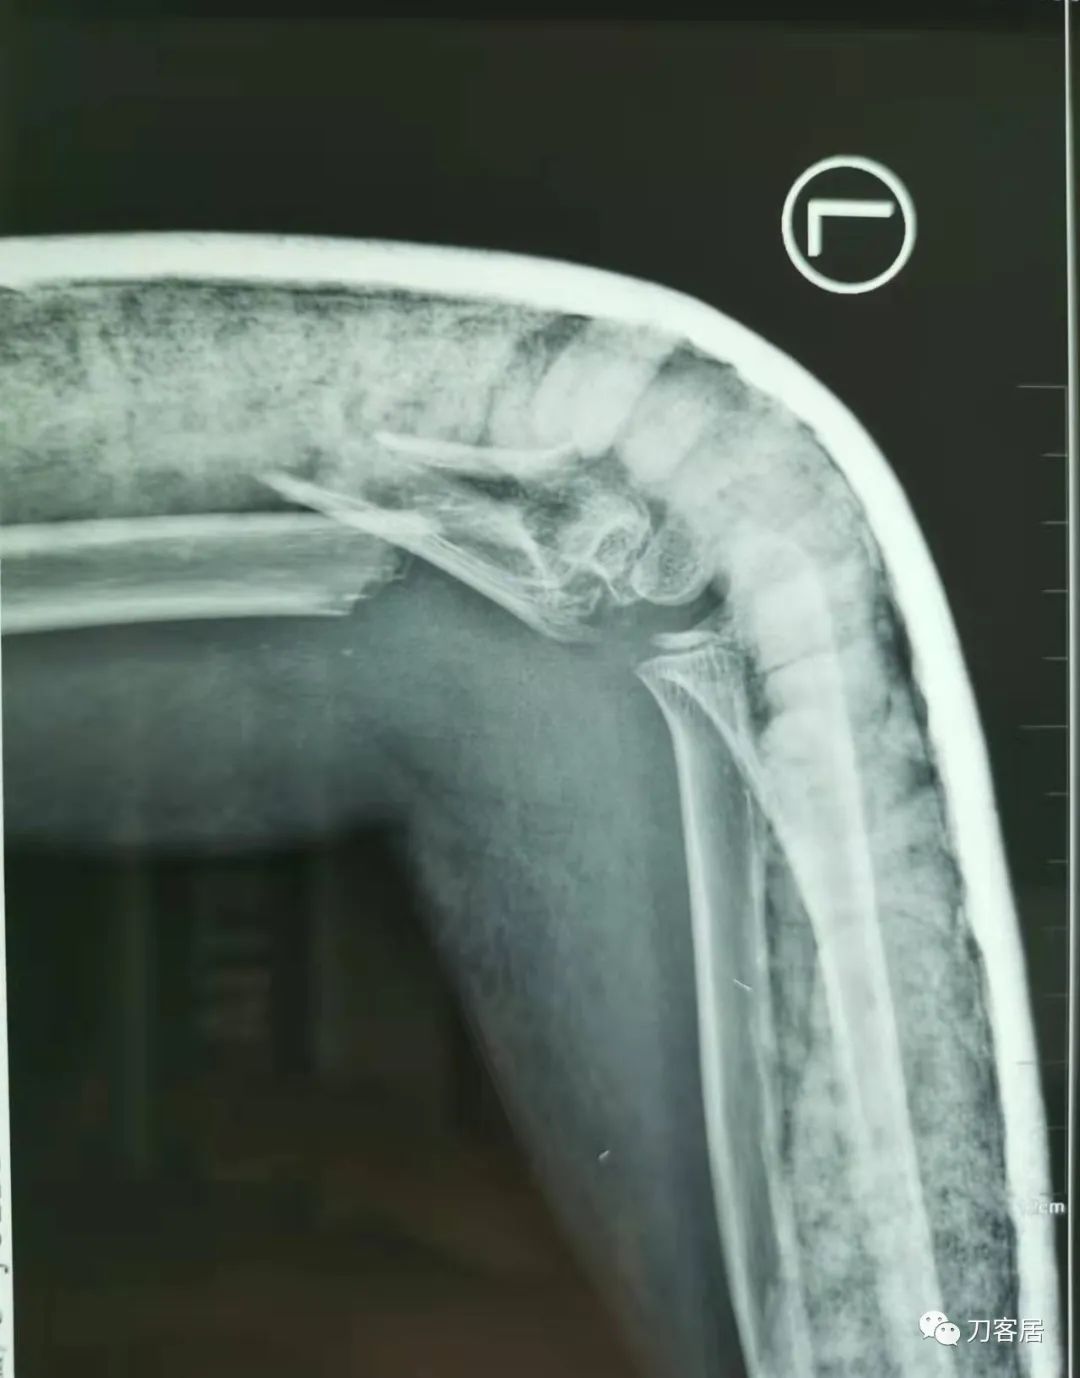

20210922当地省中医院拍摄的石膏外固定侧位X线片